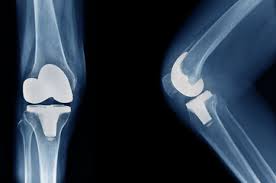

무릎 인공관절 수술, 왜 필요한가요?

무릎관절은 체중을 가장 많이 지탱하는 관절입니다. 나이가 들수록 연골은 점차 마모되고, 충격을 흡수하는 능력도 감소합니다. 이로 인해 통증, 뻣뻣함, 운동 제한이 생기며, 이런 증상이 악화되면 인공관절 수술이 필요해집니다.

퇴행성 관절염 외에도 류마티스 관절염이나 외상 후 관절 손상이 심각할 경우 수술이 권유되며, 수술을 통해 환자는 통증 없이 보행이 가능해지고 일상생활로 복귀할 수 있게 됩니다.